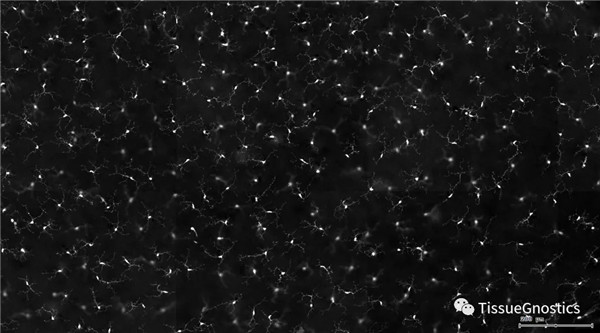

視網(wǎng)膜熒光樣本中小膠質(zhì)細(xì)胞胞體、神經(jīng)纖維識(shí)別、血管識(shí)別、血管斑點(diǎn)識(shí)別、神經(jīng)元與血管的距離分析。

單通道灰階圖(↑:FITC,↓:Texa Red)